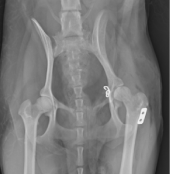

股関節脱臼の

トグルピンによる整復

治療には多くの整形疾患で手術が必要になります。術式は折れ方や場所、脱臼の場所などにより様々で、多様な方法を組み合わせて行います。

手術器具は、整形用ドリル(骨を切ったり、スクリュー(ネジ)用の穴を開けたりします)、整形用ラウンドバー(骨を削る器具です)、各種骨プレート・スクリュー、ワイヤー、ロッキングプレート・ロッキングスクリュー(通常のプレートより強固な固定が可能です)、骨セメント、整形器具を揃えており、幅広い手術に対応可能です。